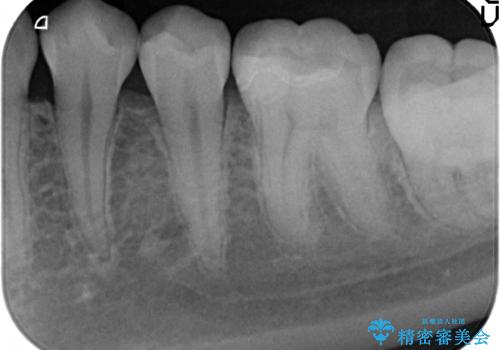

- 左下奥歯がしみるので診て欲しいといらっしゃった方の症例です。

古い樹脂と虫歯を除去後、セラミックインレーによる修復を行いました。

虫歯治療は虫歯の進行度によって処置が変わってきます。

虫歯が小さければ、インレー・クラウン等による修復・補綴処置を行うだけで済みます。

しかし虫歯が大きくなると神経処置や抜歯等をしなければならない場合もあります。

ですので虫歯治療においては早期発見・早期治療が肝要です。